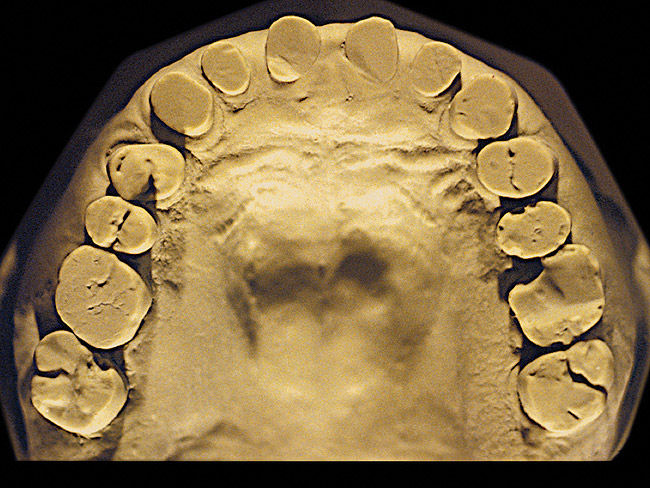

Figure 4  Advanced NCLTS from bruxism, maxillary arch.

Figure 4

The patient shown in Figure 3 and Figure 4 exhibited severe NCLTS from bruxism. Examination of the casts indicated that the NCLTS was progressively greater toward the anterior teeth. Cupping and cratering was not present because there was no secondary cause. Figure 5 and Figure 6 detail another bruxism patient, but to a lesser degree and one with cupping/cratering caused by toothpaste. The cups or craters were not caused from bruxism because the teeth could not touch the bottom of the invaginations. In both featured patients, upon hand-articulating the casts, the NCLTS facets matched up and the diagnosis of bruxism was confirmed.